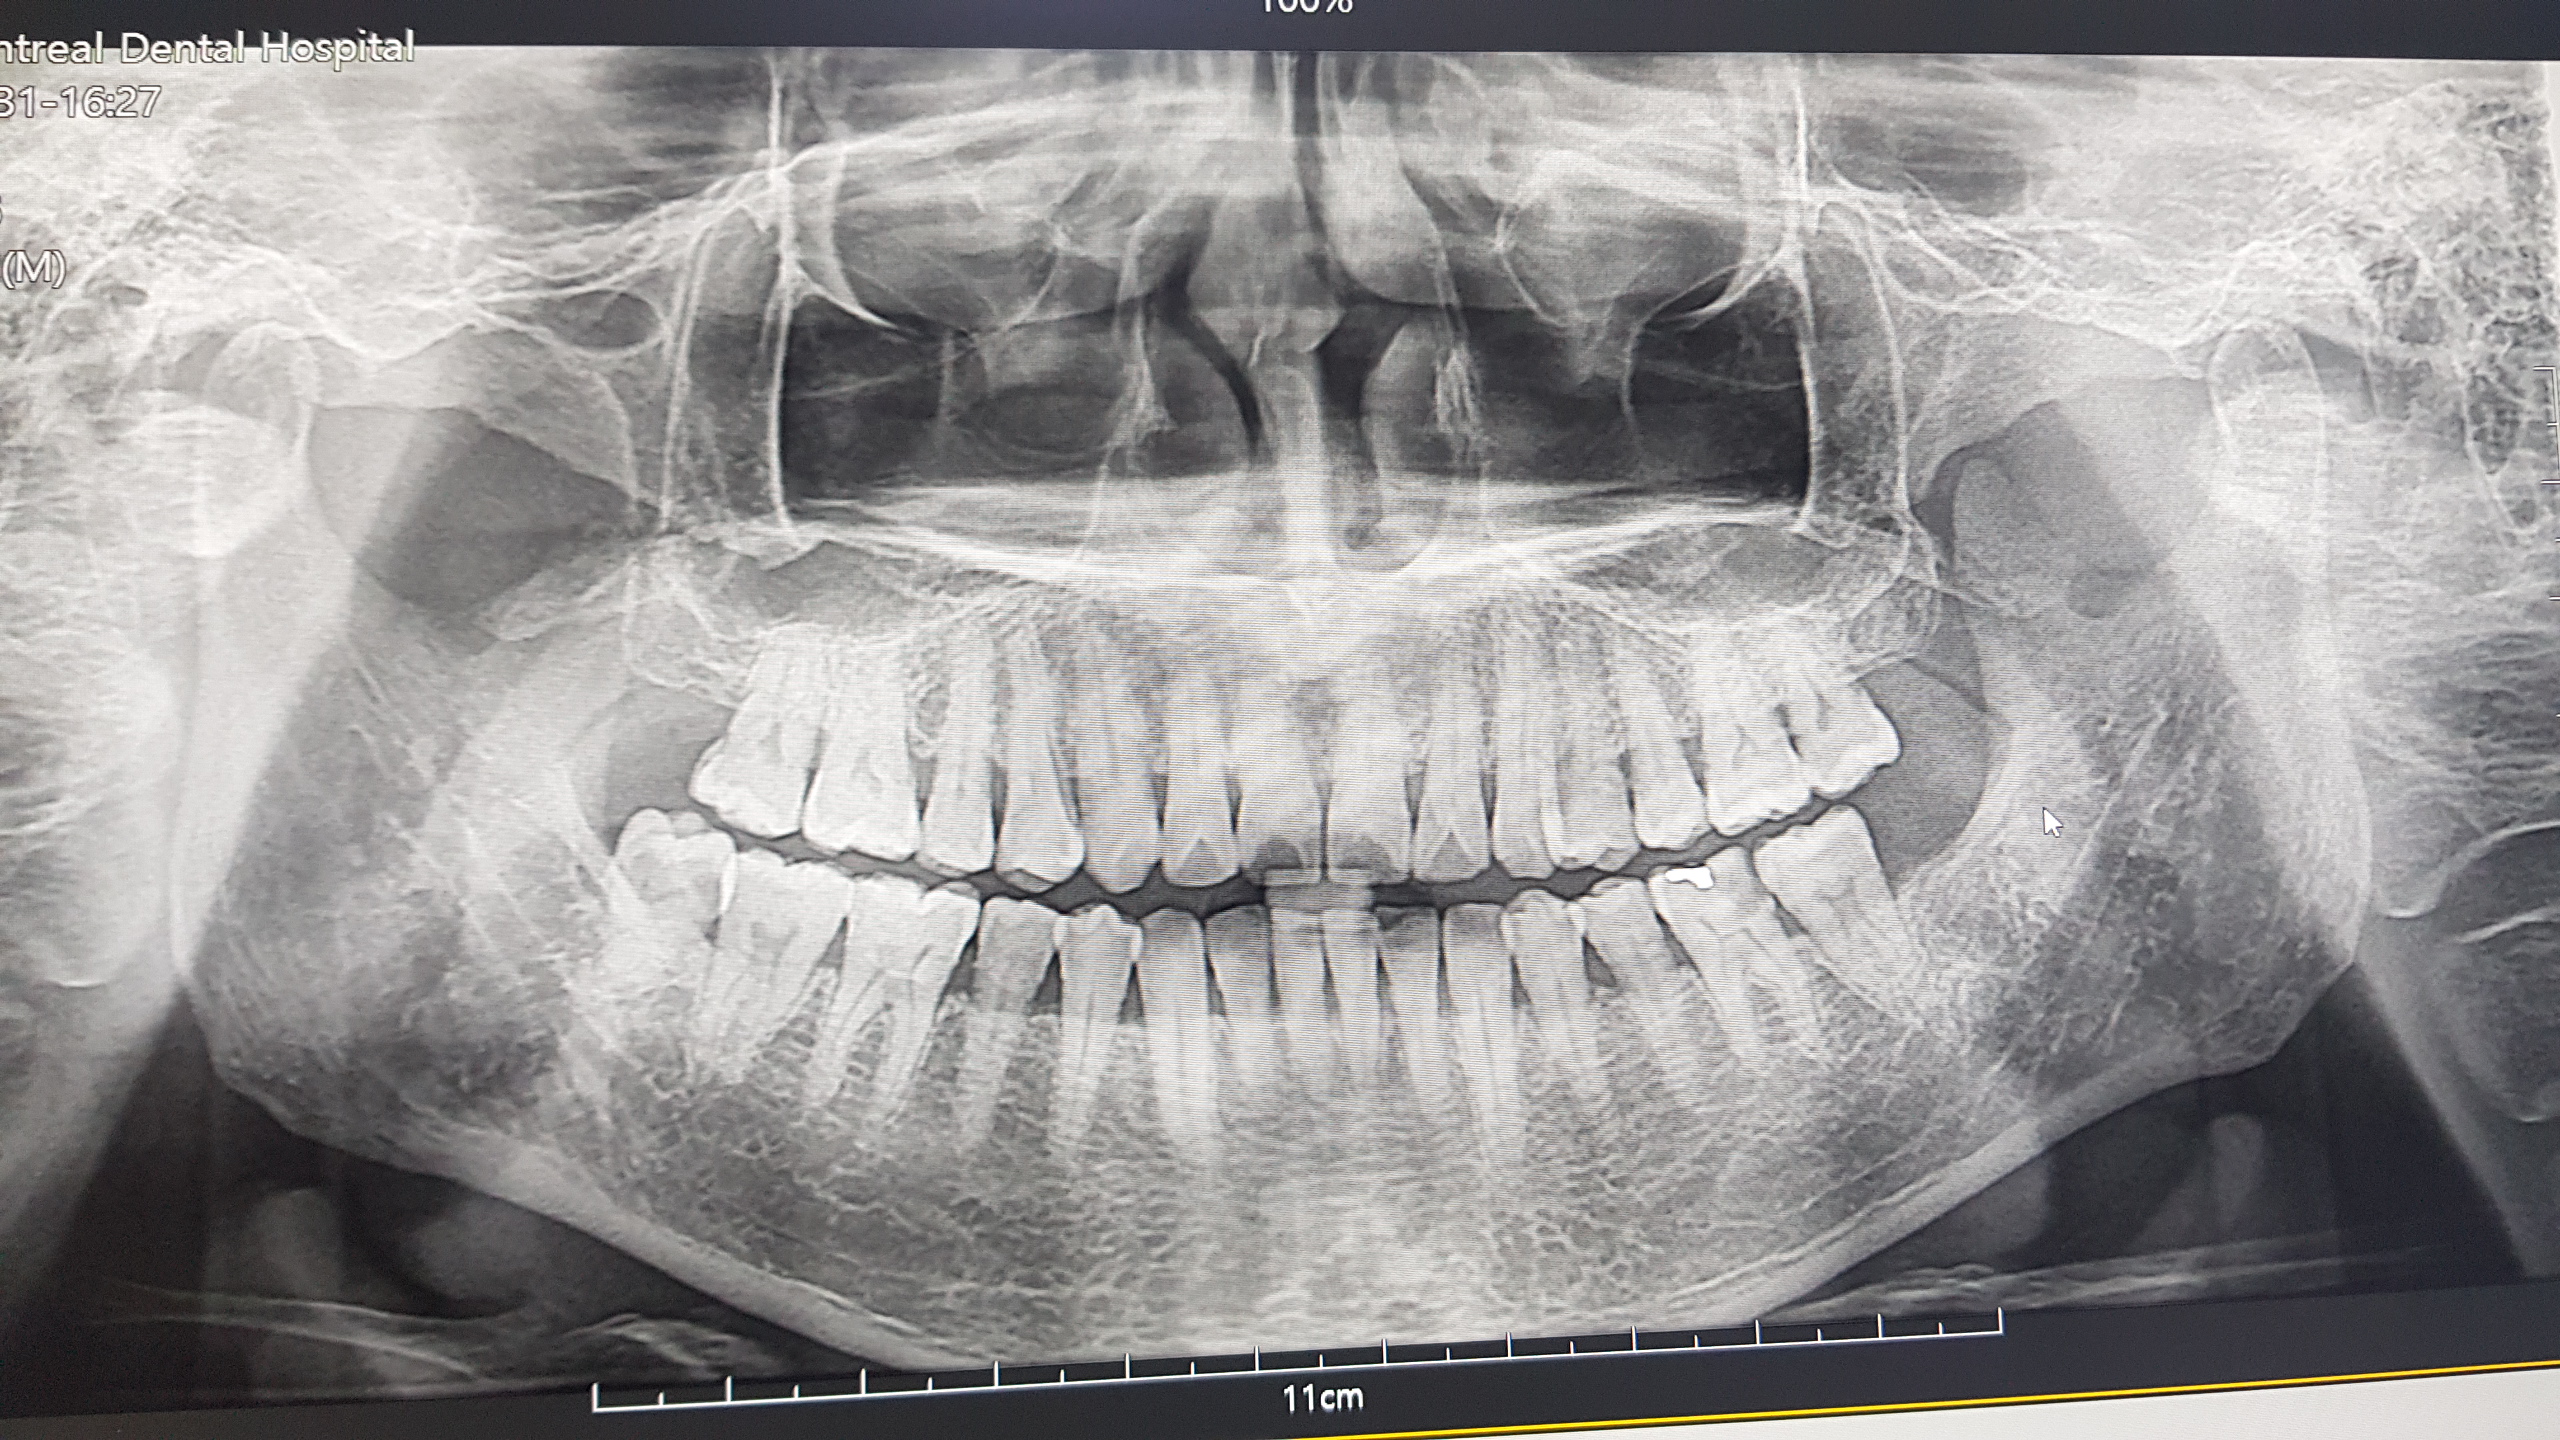

일단 ..또다시 엑스레이를 찍고..

여기서도..신경 치료를 해야한다고 한다.